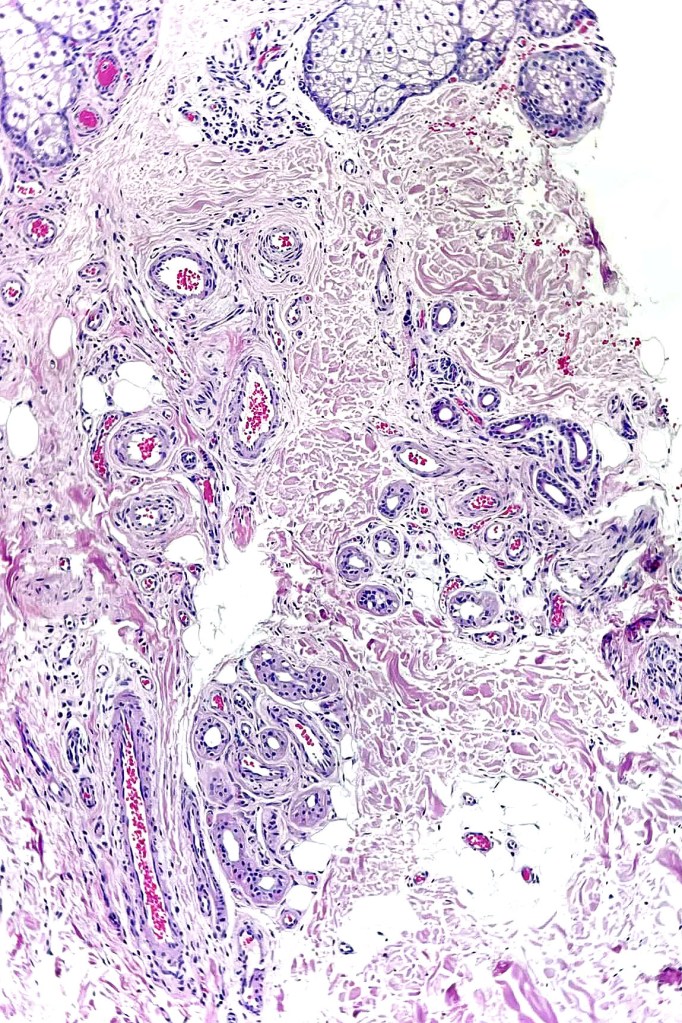

Histological features

•Hyperkeratosis & variable acanthosis & papillomatosis

•Mid- to deep dermal lobular infiltrate of sweat glands & ducts accompanied by capillaries & small vessels

•In some cases, larger venules & veins are present & associated arteriovenous malformation, spindle cell hemangioma, angiokeratoma & verrucous hemangioma have been described

•Variable adipose, smooth muscle, neural & apocrine components